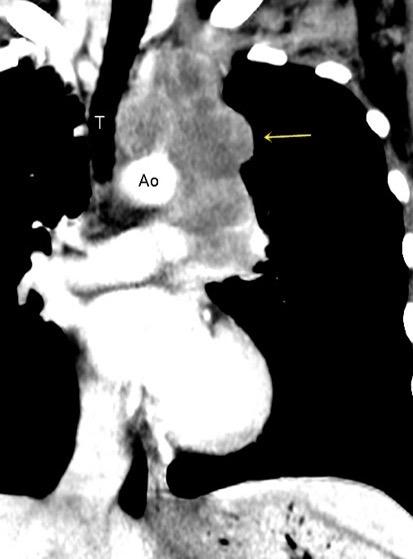

“Draped aorta”.

Indica rotura aórtica reciente. Se manifiesta por una pared aórtica posterior o el contacto con el borde lateral vertebral borrados por la hemorragia.

Rotura aneurisma de Aorta descendente.

Dolor. (10 días antes: "Rotura inminente”)